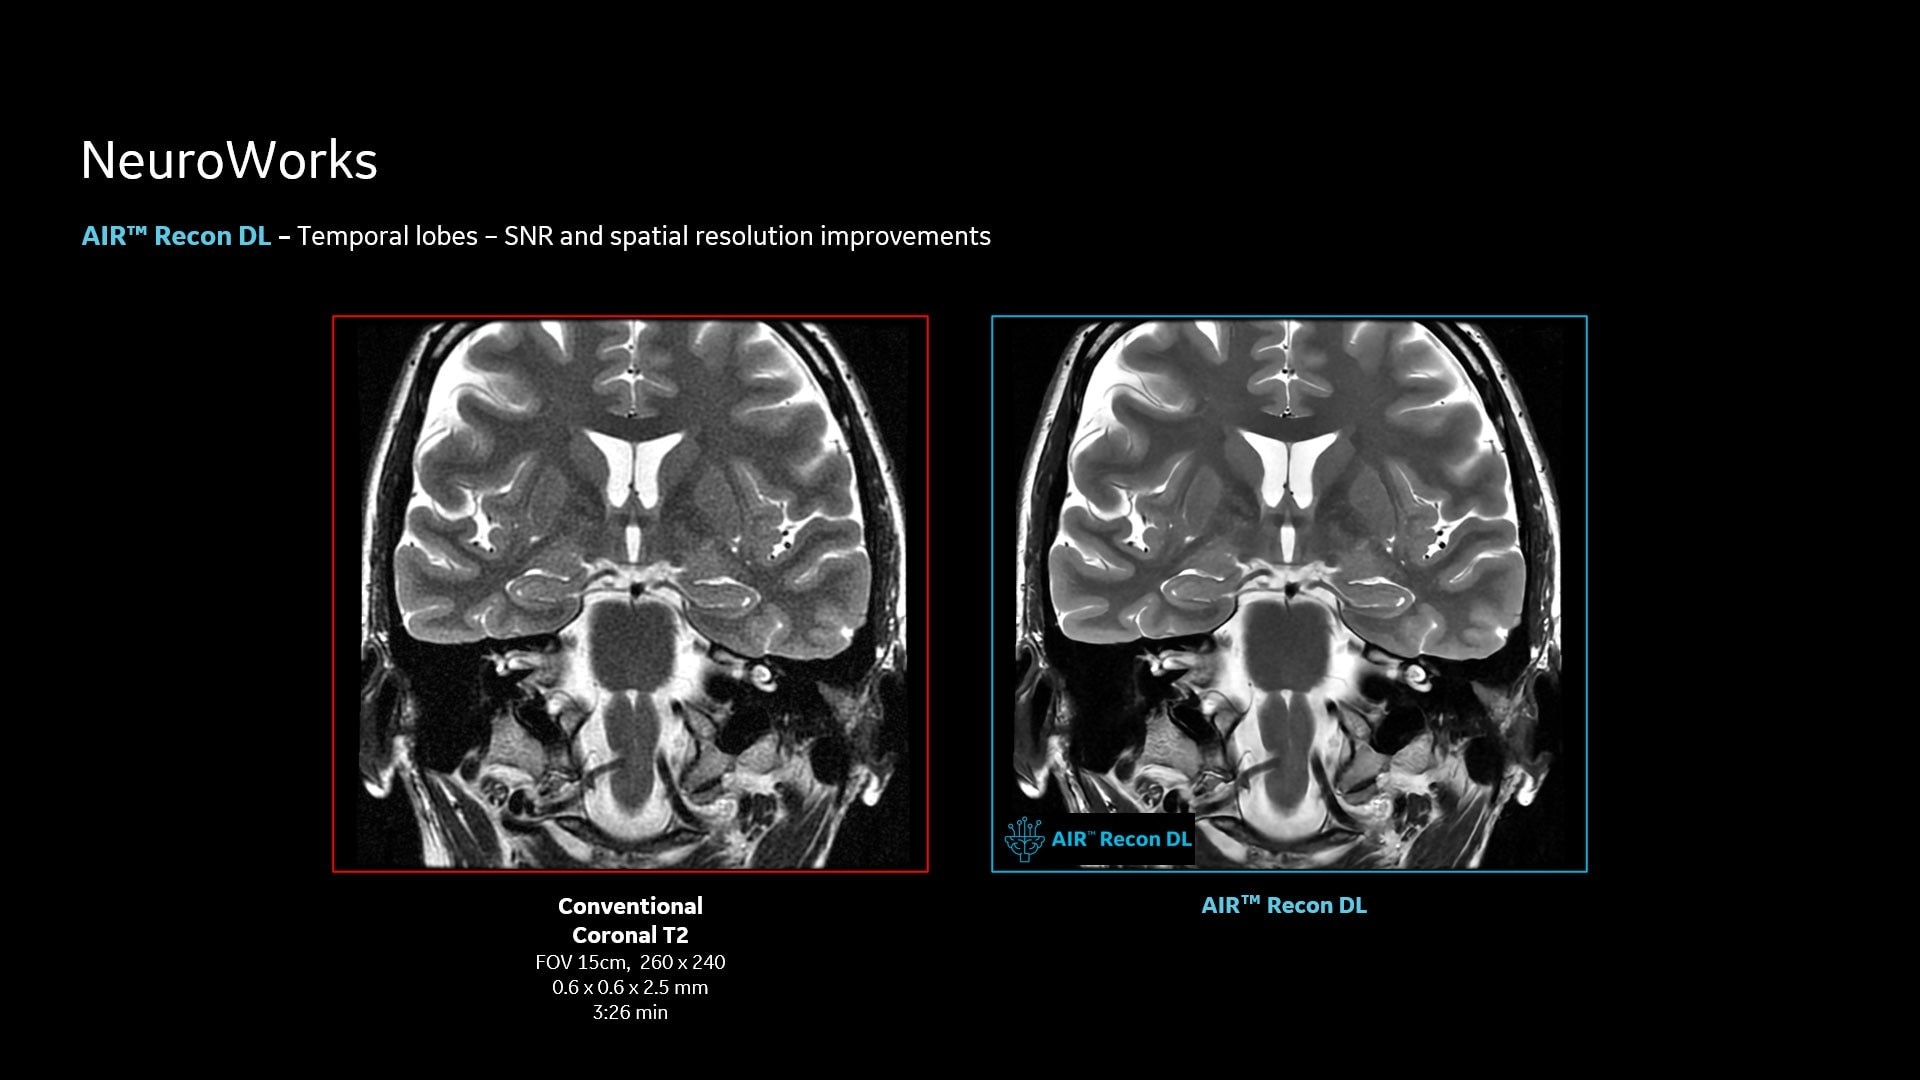

AIR™ Recon DL improves SNR and image sharpness, enabling shorter scan times

Achieve a 25% efficiency gain with Ultra High Efficiency (UHE) gradient system. Fast, clear Total Digital Imaging (TDI) increases SNR by 25%. Improved IQ in 80% of cases without added time. Acquire higher SNR without a time penalty and get images virtually free of artifact with AIR™ Recon DL.***